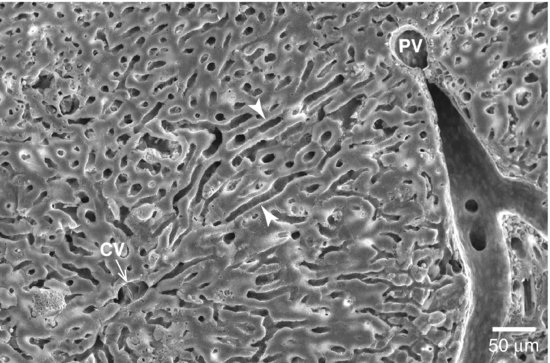

Figure 1. Figure 1. Rat liver lobule. Scanning electron micrograph of the lobule structure of rat liver. Numerous sinusoids (arrow heads) are seen connecting portal venules (PV) with central venules (CV), with the liver parenchyma surrounding the sinusoids. Blood flows from the portal venule to the central venule through the sinusoids. Scale bar: 50 μm.

Figure 1. Rat liver lobule. Scanning electron micrograph of the lobule structure of rat liver. Numerous sinusoids (arrow heads) are seen connecting portal venules (PV) with central venules (CV), with the liver parenchyma surrounding the sinusoids. Blood flows from the portal venule to the central venule through the sinusoids. Scale bar: 50 μm.